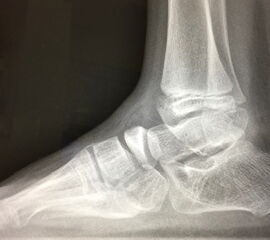

Zusätzlich schränken Wachstumsfugen die Wahl der Osteosynthese ein. Eine die Fuge kreuzende Osteosynthese ist ausschließlich mit Kirschner-Drähten möglich (Abb. 3).

Abb. 3 a-j: Beispiel einer Calcaneusverschiebeosteotomie mit offenen Wachstumsfugen und der entsprechenden Osteosynthese mit Kirschner Drähten. Lokalisation der Osteotomie (a), Lage der Fräse (b-d), Drahtlage mehrere Ansichten (e-h), Heilung der Osteotomie 4 Wochen postoperativ und Entfernung der Drähte (i-j).